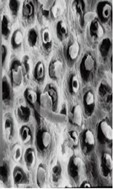

采用牙科用磷酸酸蝕劑對牙釉質(zhì)表面進(jìn)行酸蝕處理,可清除釉質(zhì)表面的涎液沉積物、菌斑及其他附著物,使表面羥基磷灰石礦物質(zhì)不均勻脫礦,形成凹凸不平的蜂窩狀表面結(jié)構(gòu),見圖1。這種結(jié)構(gòu)不但增加了粘接的表面積,而且能夠使粘接劑與釉質(zhì)間形成微機(jī)械嵌合作用,產(chǎn)生牢固的結(jié)合力。

圖1 牙釉質(zhì)表面酸蝕前后形態(tài)掃描電鏡圖示例

如圖1所示,(左)酸蝕前,正常的牙釉質(zhì)表面致密;(右)酸蝕后,表面不均勻脫礦,呈現(xiàn)蜂窩狀結(jié)構(gòu)。